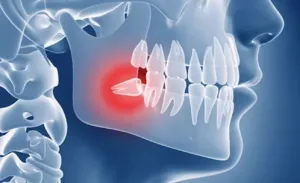

Особливості зубів мудрості та їхній вплив на здоров’я ротової порожнини Що таке зуби мудрості...